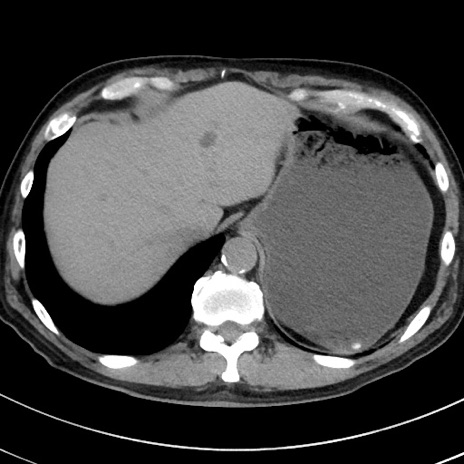

症例38(横断像)

【症例】70歳代 男性

【主訴】腹痛・嘔吐

【現病歴】昨晩より、嘔吐・腹痛あり。今朝になっても嘔吐あり。来院。

【既往歴】心臓バイパス手術、開腹胆摘、腸閉塞

【身体所見】BP 107/71mmHg、HR 116/min、腹部:平坦、軟、下腹部に軽度圧痛あり。反跳痛なし。

【データ】WBC 15100、CRP 0.32